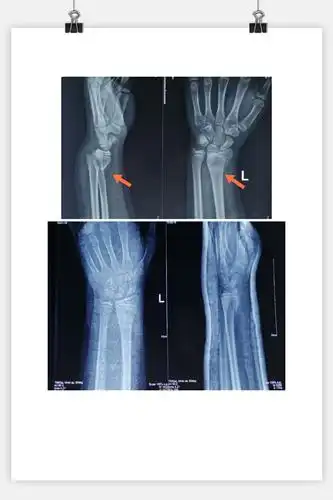

【手法整复】桡骨远端骨折

桡骨远端骨折手法复位一例